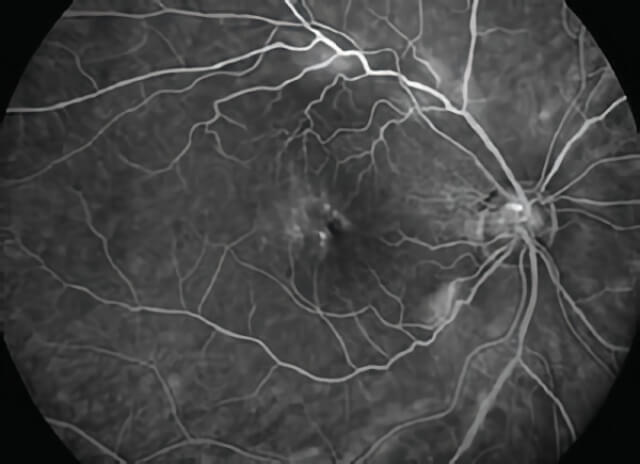

Fluorescein angiogram image in a patient with VMT, showing distortion of the retinal blood vessels and white “clouds” indicating fluid accumulation in areas of traction, especially in the center and upper portion of the image.

A careful retinal examination can reveal signs of VMT, including distortion and elevation of the retina and fluid accumulation within areas of stretched retina. Specialized tests such as a photographic assessment of the retinal blood flow after injection of an intravenous dye called a fluorescein angiogram and a computerized optical scan of the retina called an OCT can help in making the diagnosis and in determining the severity of VMT.